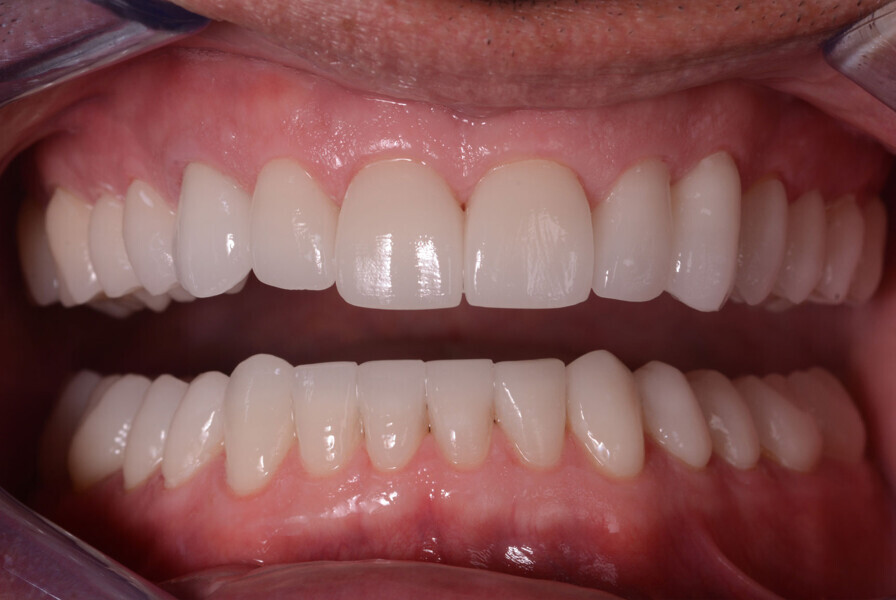

Fig. 11: The crowns (#11–13 and 21–23) and veneers (#14–17, 24–27, 31–37 and 41–47) were secured to the abutments using a light-cured resin adhesive (Futurabond U and Bifix QM).

Fig. 12: The crowns (#11–13 and 21–23) and veneers (#14–17, 24–27, 31–37 and 41–47) were secured to the abutments using a light-cured resin adhesive (Futurabond U and Bifix QM).

Fig. 13: Intraoral photographs after treatment.

Figs 14: Intraoral photographs after treatment.